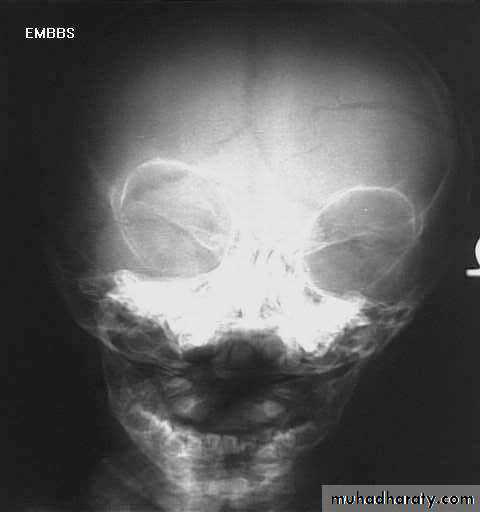

Skull Fracture

1. Can demonstrate the site and type of a skull fracture.2. A foreign body can also be seen.

Indications for skull x-ray in head injury

• Impaired consciousness or neurological signs.• History of loss of consciousness, amnesia, or fits.

• High speed injury or suspected penetrating injury.

• Scalp laceration to bone, large haematoma, or suspected fracture on palpation.

• Persisting vomiting or headache.

• Loss of cerebrospinal fluid or blood from ear or nose.

• Difficulty in assessing the patient (children, drug or alcohol intoxication).